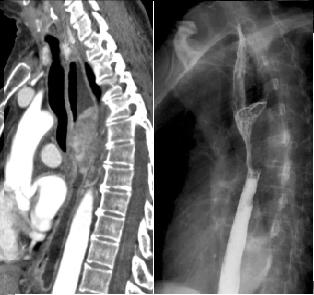

Adeno carcinoma de oesophage

1/3 a inferieure de oesophage .Image en coupe

coronale ( frontale ) |

Image TDM

encoupe axiale : Cancer de oesophage |